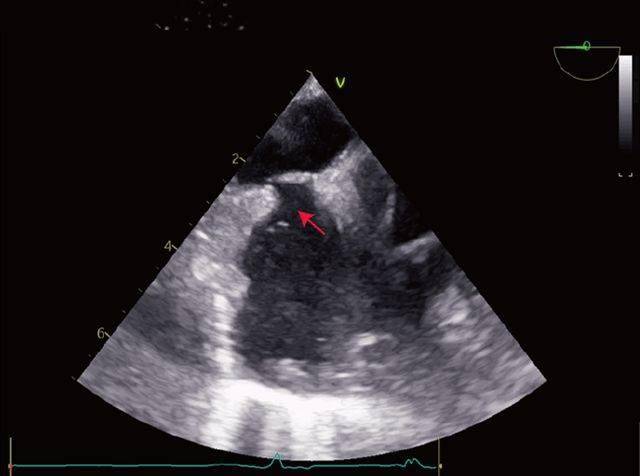

超声心动图和dsa引导下,经股静脉入路,在距二尖瓣环40mm处穿刺房间隔

食管中段切面:左房,左室内大量气泡床旁行腹部超声及经食道超声心动图